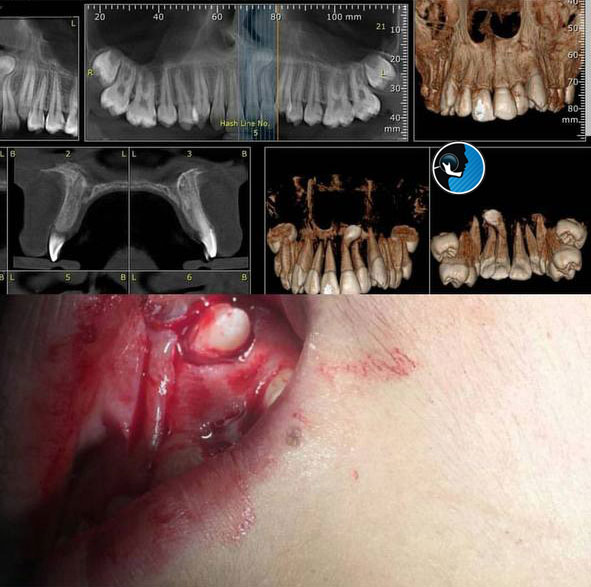

اکسپوژر دندان نهفته چیست؟ راهنمای کامل از تشخیص تا درمان

اکسپوژر دندان نهفته دندانهای نهفته یکی از مشکلات شایع در حوزه دندانپزشکی و بهویژه ارتودنسی هستند. این دندانها در زیر لثه باقی میمانند و بهدرستی در جای خود قرار نمیگیرند. یکی از روشهای رایج برای درمان این مشکل، اکسپوژر دندان…